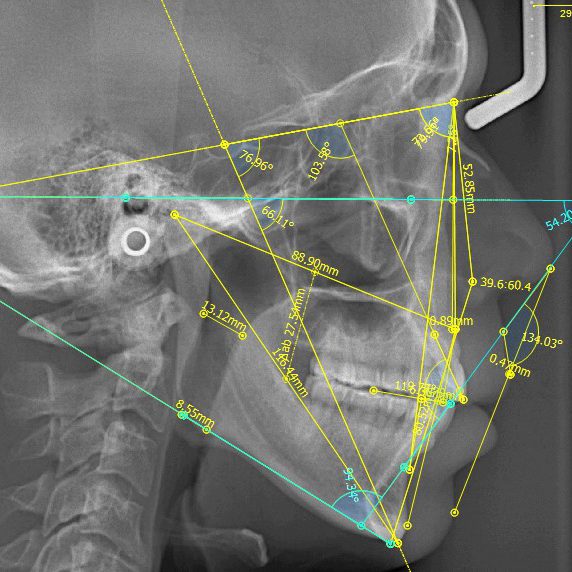

Trace your cephs with less work and more speed! Cephworx guides you through the tracing process without all the extra stuff you don't need or want. Cost effective with free lifetime standard support, Cephworx is the modern way to trace cephalometrics!